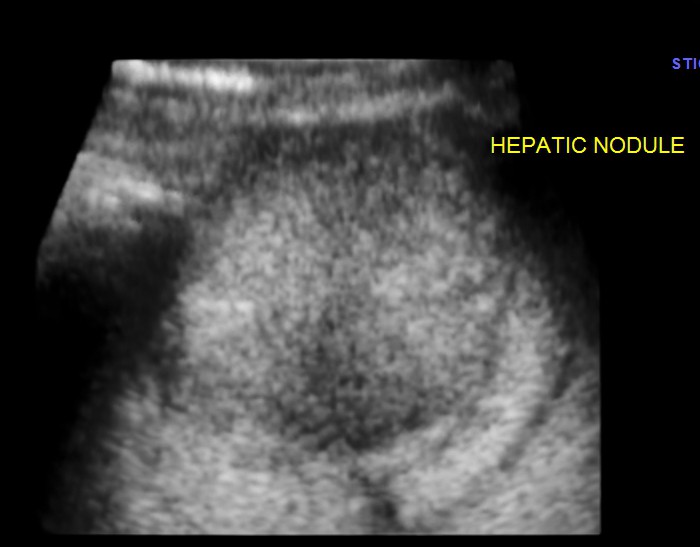

An echogenic nodule with vascularity is seen.

The appearance of this nodule was suggestive of a metastatic nodule with the increased vascularity around and within.